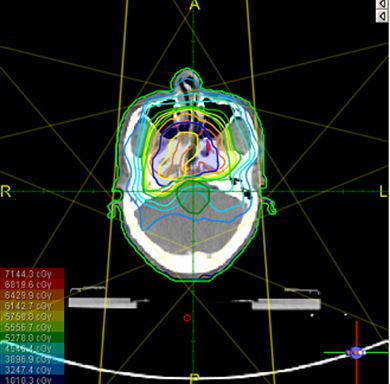

* Xác định số trường chiếu, góc chiếu, số lượng các trường chiếu chia nhỏ (segments), năng lượng chùm tia 6 MV hay 15 MV. Số lượng các trường chiếu tuỳ thuộc từng trường hợp cụ thể và kỹ thuật xạ trị lựa chọn. Có thế lập kế hoạch xạ trị 3D hoặc xạ trị điều biến liều - IMRT (Intensity Modulated Radiation Therapy) - tập trung liều bức xạ cao nhất vào tổn thương (khối u, hạch...) và thấp nhất vào tổ chức lành xung quanh (cơ quan cần bảo vệ), giảm biến chứng xạ trị. Xạ trị điều biến liều trên hình PET/CT mô phỏng hiện nay là kỹ thuật tiên tiến nhất, mang lại hiệu quả điều trị cao và giảm biến chứng xạ trị tối đa cho người bệnh.

Kiểm tra bản đồ đồng liều

Kiểm tra liều trên hình ảnh 3D

Kiểm tra liều trên DVH: liều vào GTV, CTV, các cơ quan cần bảo vệ. So sánh giữa kế hoạch 3D và IMRT: đường liền nét là đường đồng liều của kế hoạch IMRT, đường đứt nét là đường đồng liều của kế hoạch xạ trị 3D. Nhận thấy rõ là trong kế hoạch IMRT, đường liều vào GTV và CTV tốt hơn kế hoạch 3D, liều vào các cơ quan cần bảo vệ đều thấp hơn hẳn so với kế hoạch 3D.

Hình 7: Đặt các trường chiếu, tính liều, kiểm tra trên bản đồ đồng liều, hình 3D và DVH.